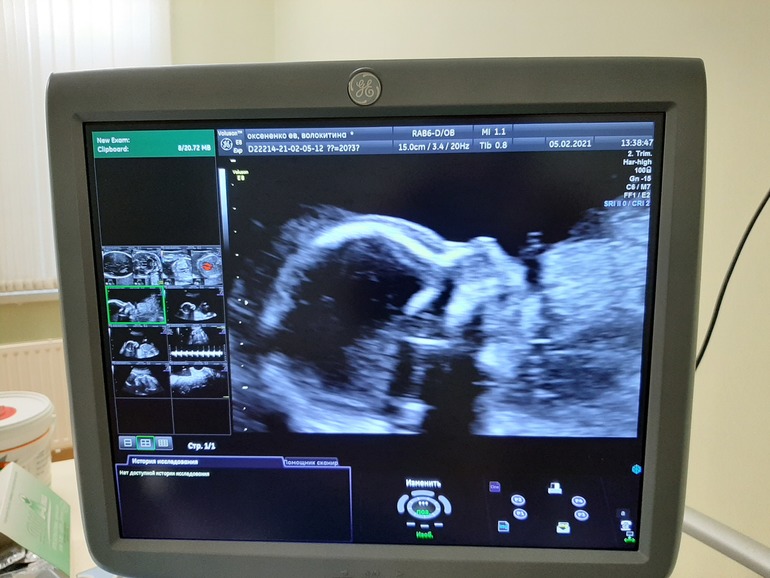

Ах ну и фото, с монитора правда, нашей Евишны-королевишны, оооох так и приалепится имя 🤷♀️....

Говорю, на меня похожа, врач посмотрела говорит, нет нос не ваш 🤣🤣🤣. Чтобы она понимала 🙈🤣

Ну да ладно. Пришла на УЗИ, врач смотрела в основном молча, напряглась не много, но не много терпения, как все замеры сделала, только потом задала ей несколько вопросов, по УЗИ все хорошо сердечко 151 чсс, спросила кто там)), она сказала мне кажется девочка, таааак как это кажется 🤣, переспрашиваю: "Точно?" Она улыбается и между делом: "Точно!". А мне снова не верится)))) Но других вариантов нет, я с первого дня чувствую дочку, боюсь поверить, но там точно не парень😂.

336 гр, нашего счастья😍😍😍!!